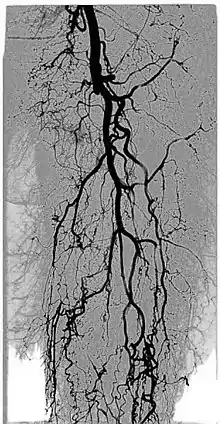

Digital variance angiography (DVA)

The diagnostic value of radiographic images is limited by image quality, which can be measured through signal-to-noise ratio (SNR) calculations. The higher the value of SNR, the better the image. The SNR can be increased initially by enhancing the "signal" or "contrast", which is the intensity difference between the object of interest and the background. This is usually done by adding contrast medium to increase the attenuation values of the object, while holding the background values constant.[1][2][3][4]

By allowing visualization of movements, kinetic imaging offers a new type of motion-based contrast. In many cases, the kinetic image will have a higher SNR (better image quality) compared to traditional images for moving objects.[2][6][1][3][4]

This improvement in SNR and image quality has been studied by Gyánó M. et al. (2018)[3] and Óriás V. et al.(2019)[4] in the field of traditional angiographic imaging and carbon-dioxide imaging. Their findings indicate that by using the kinetic imaging (or as they called this method in the case of angiographies, digital variance angiograpy, DVA) for processing angiographic image sequences, the quality improvement may increase diagnostic insight and it also creates a quality reserve, which means that DVA could provide the same level of image quality, as the gold-standard DSA technique, but the dose of administered radiation and/or contrast agent could be lowered.[3]